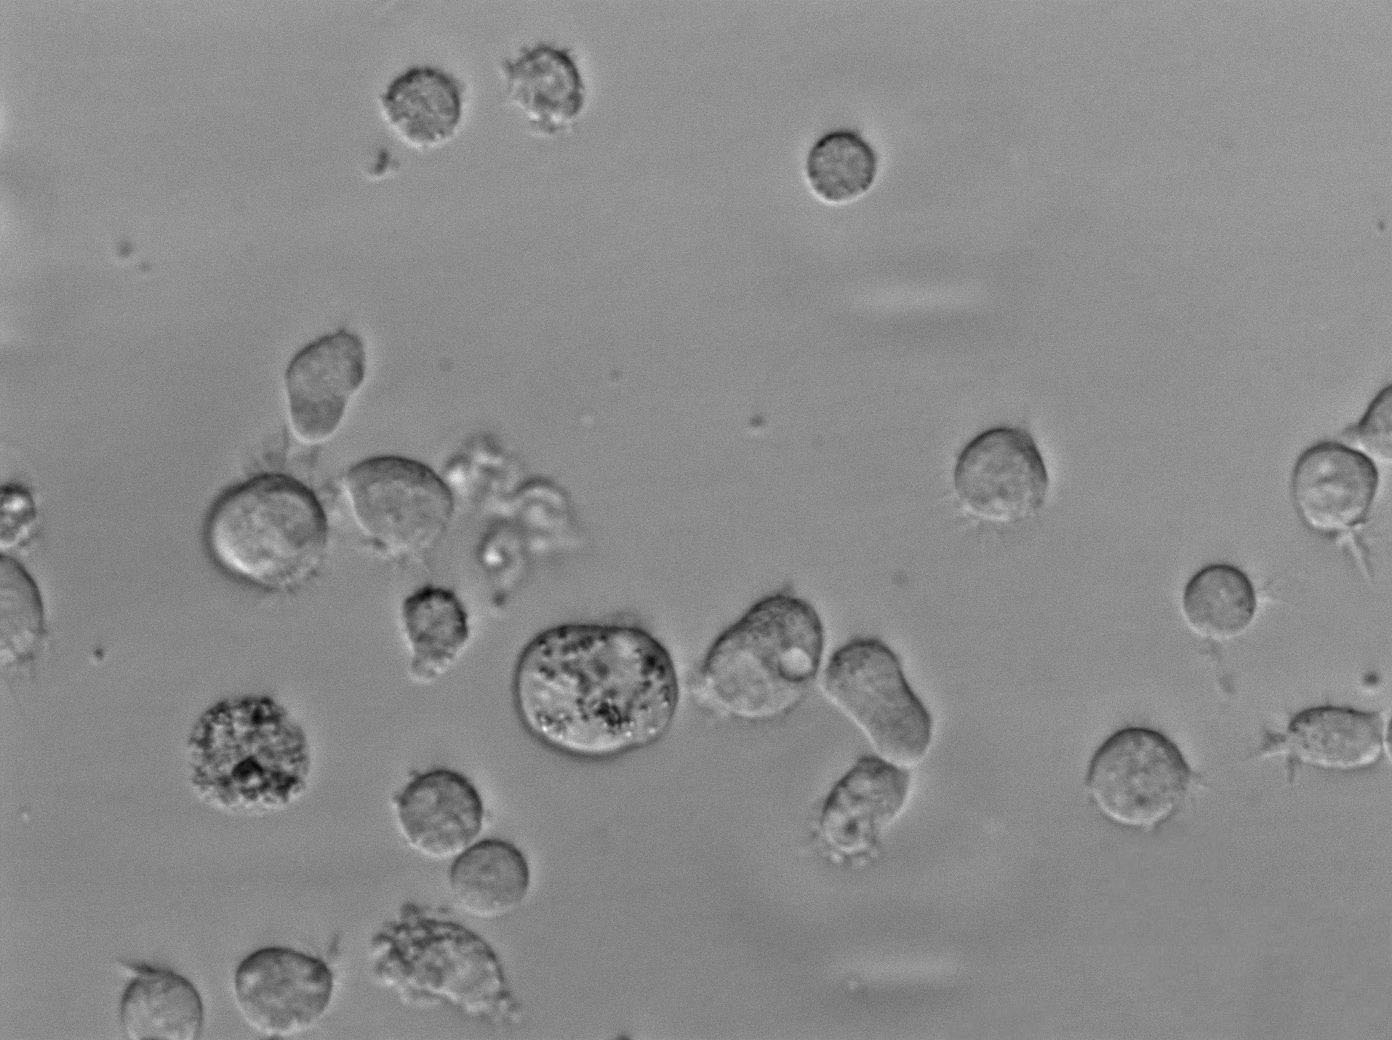

SUP-B1:人Ph+急淋白血病复苏细胞(提供STR鉴定图谱)

细胞生长:悬浮

细胞形态:淋巴母细胞样

细胞传代方法:1:2-1:3传代;每周换液2-3次。